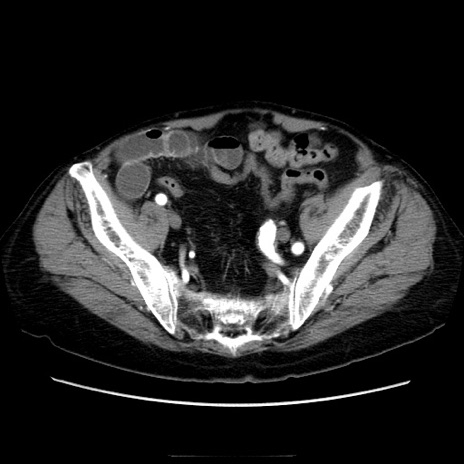

症例21(横断像)

【症例】70歳代男性

【主訴】腹痛

【現病歴】肝硬変・肝細胞癌にてかかりつけの方。約9時間前に食後より腹痛出現。症状が徐々に増悪し、嘔吐出現したため来院。

【既往歴】肝硬変、肝細胞癌(RFA、TACE後)

【身体所見】意識清明、表情苦悶様、BT 36℃、BP 129/78mmHg、P 88bpm、SpO2 97%(RA)、右上腹部から心窩部にかけて圧痛あり、反跳痛なし、筋性防御あり。

【データ】WBC 5800、CRP 0.16